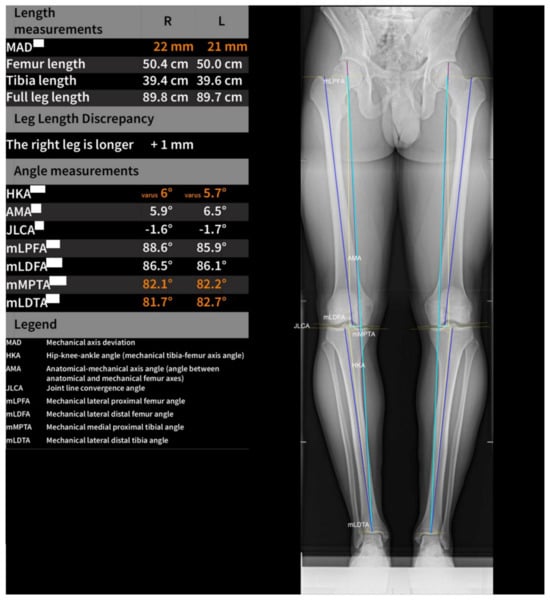

2.2. Software Measurements